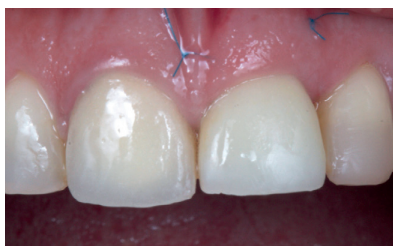

Soft tissue management with the provisional crown

The provisional was removed after 14 weeks, when the gingival margin was seen to be correctly positioned, along with 100% coverage of the recession, complete papillae maintenance and a correct emergence profile (Figures 14 and 15). However, from an occlusion view, there was a lack of buccal volume with respect to the adjacent tooth. Work began with the provisional crown, with progressive increases of composite in the subcritical profile, until a volume similar to tooth 1.1 was achieved. These increases were performed every 15 days (Figure 16)13.